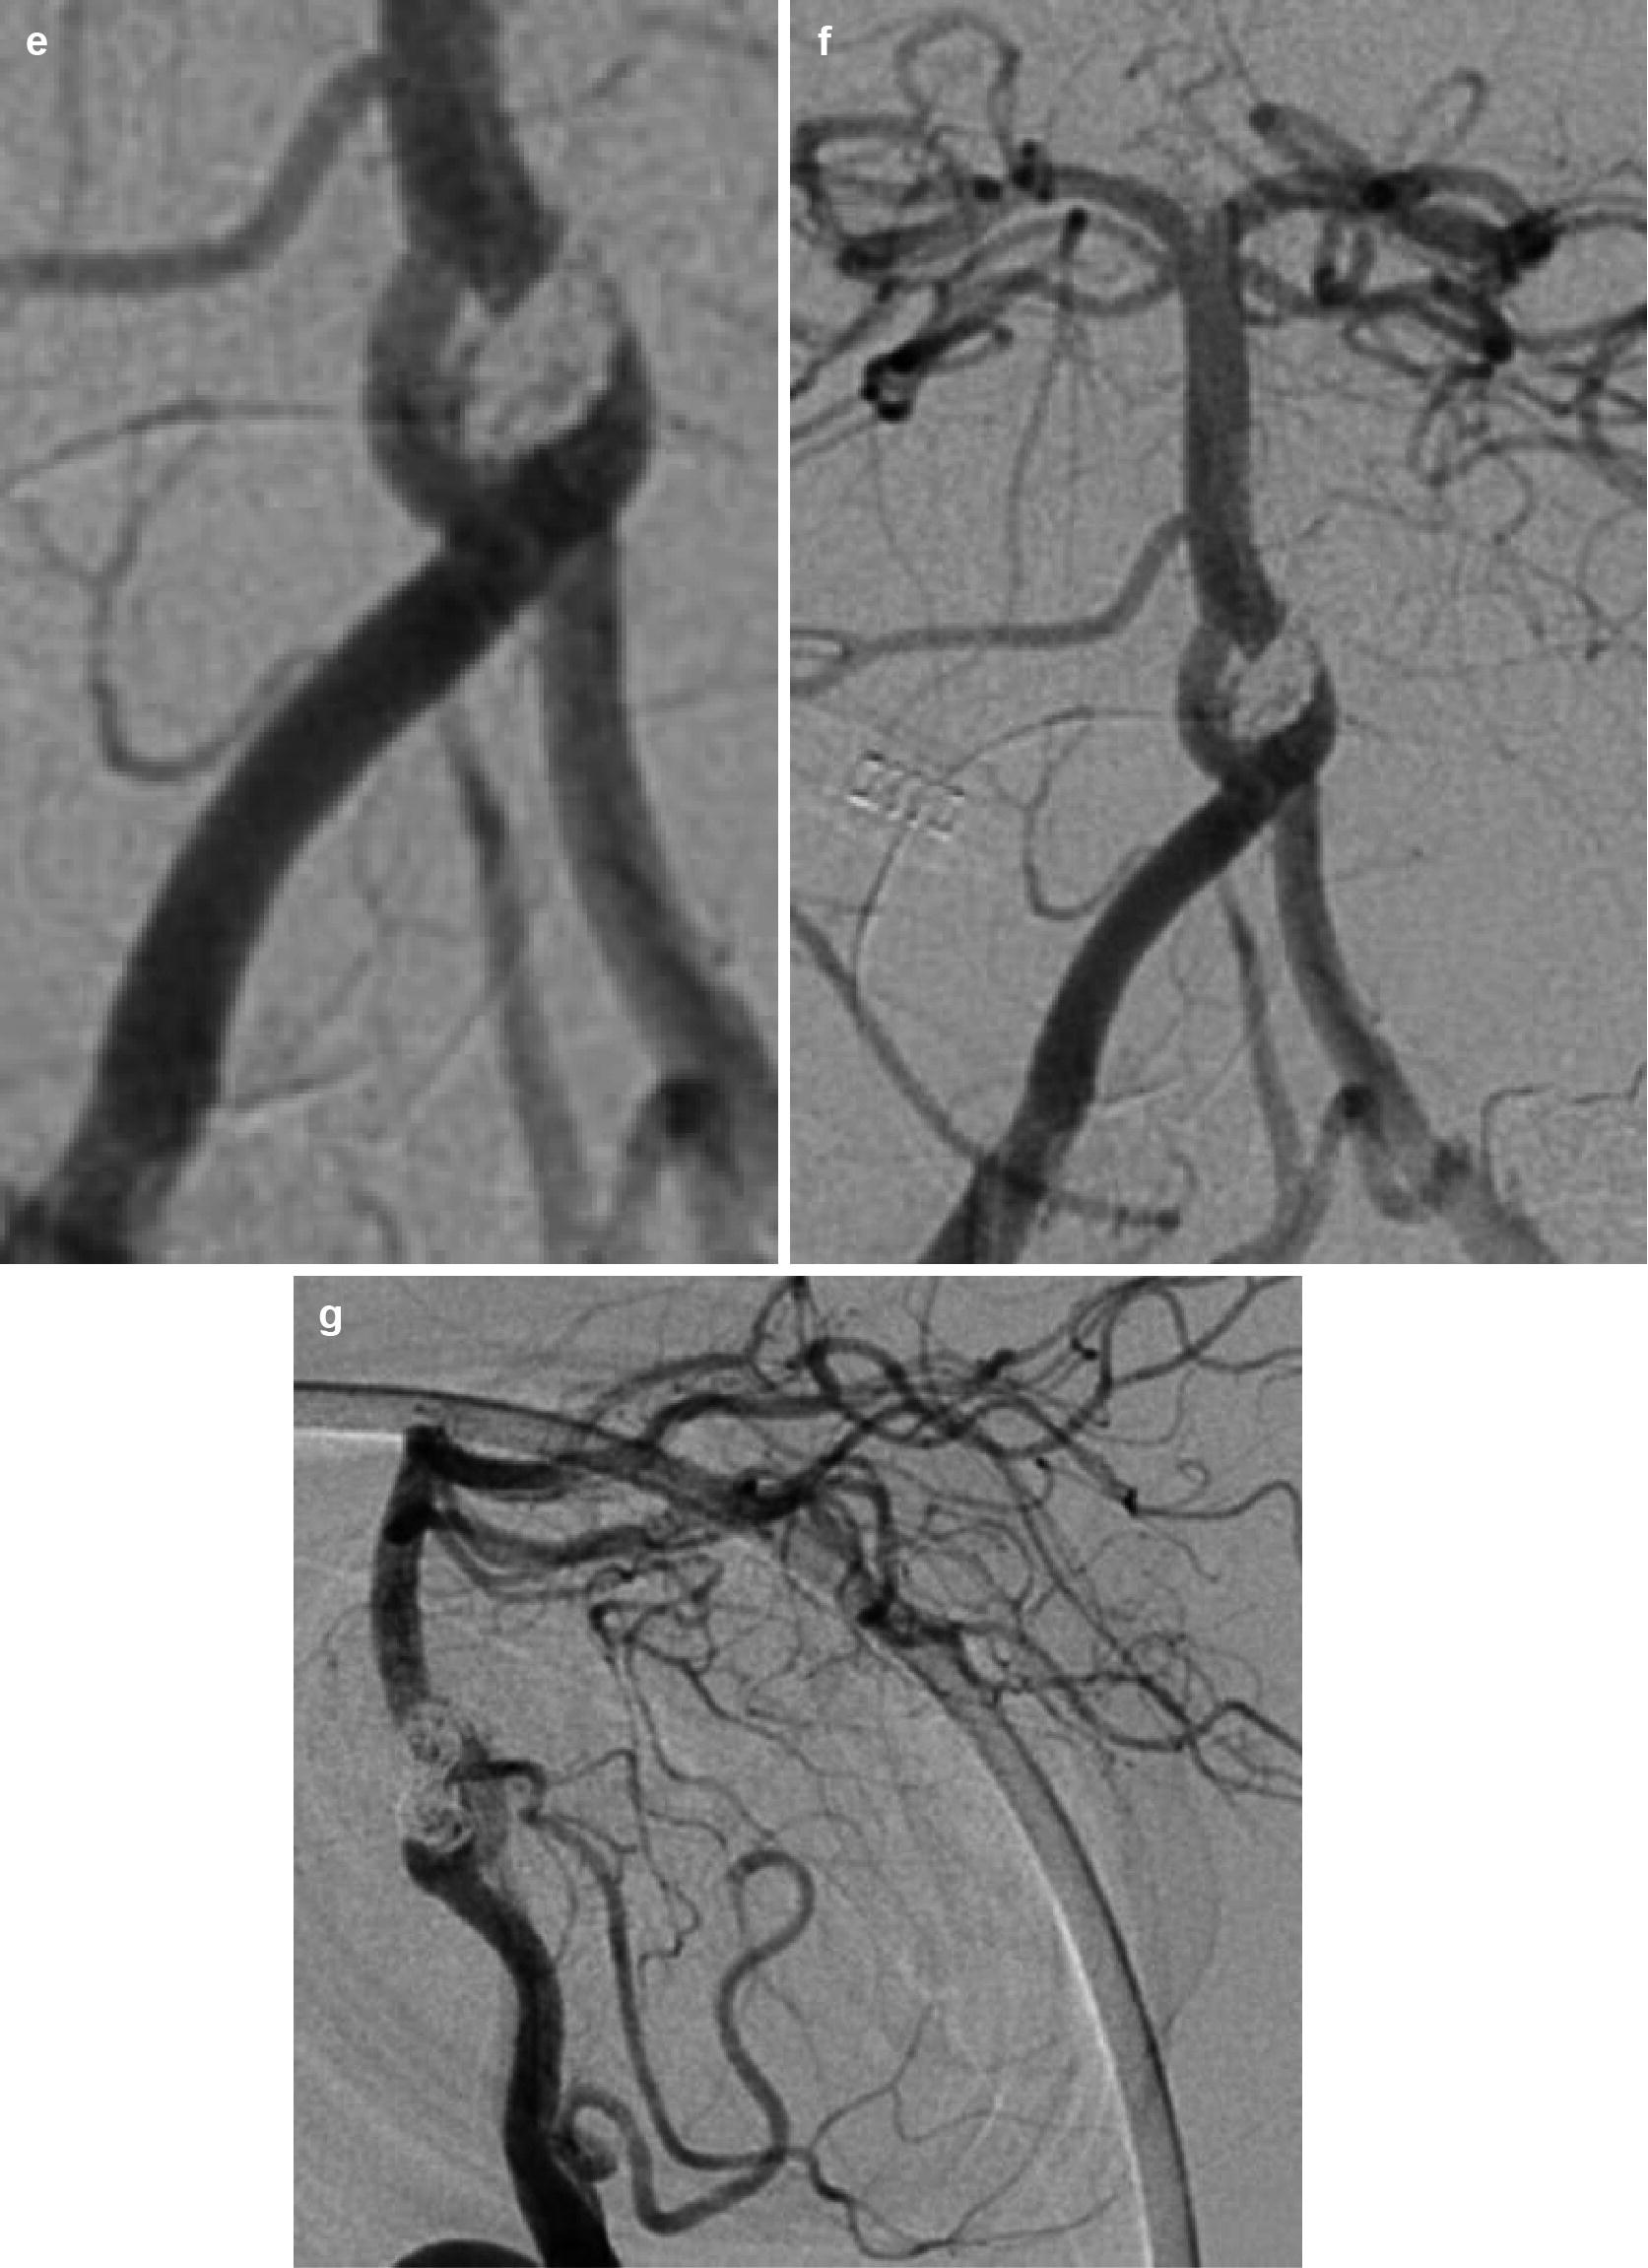

Techniques of Endovascular Aortoiliac Repair Using an Iliac Branch

Techniques of Endovascular Aortoiliac Repair Using an Iliac Branch Coil Occlusion Aneurysm What is coil occlusion of aneurysm? Our study shows that 3.7% (95% ci, 2.7% to 4.9%) of patients have complications with a permanent deficit from endovascular. Because their use was cumbersome and associated with high incidence of. This is an endovascular treatment which means it is performed through a blood vessel by a consultant interventional neuroradiologist. Proportion of aneurysms with. Coil Occlusion Aneurysm.